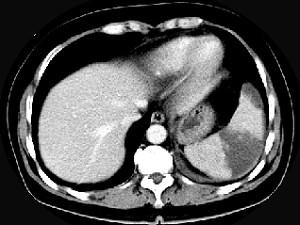

女、54岁,左上腹痛,CT检查如图,最可能的诊断是 ( )A、脾血管瘤B、脾转移瘤C、脾脓肿D、脾梗死E、脾淋巴瘤

问题 女、54岁,左上腹痛,CT检查如图,最可能的诊断是 ( )

选项 A、脾血管瘤 B、脾转移瘤 C、脾脓肿 D、脾梗死 E、脾淋巴瘤

答案 D